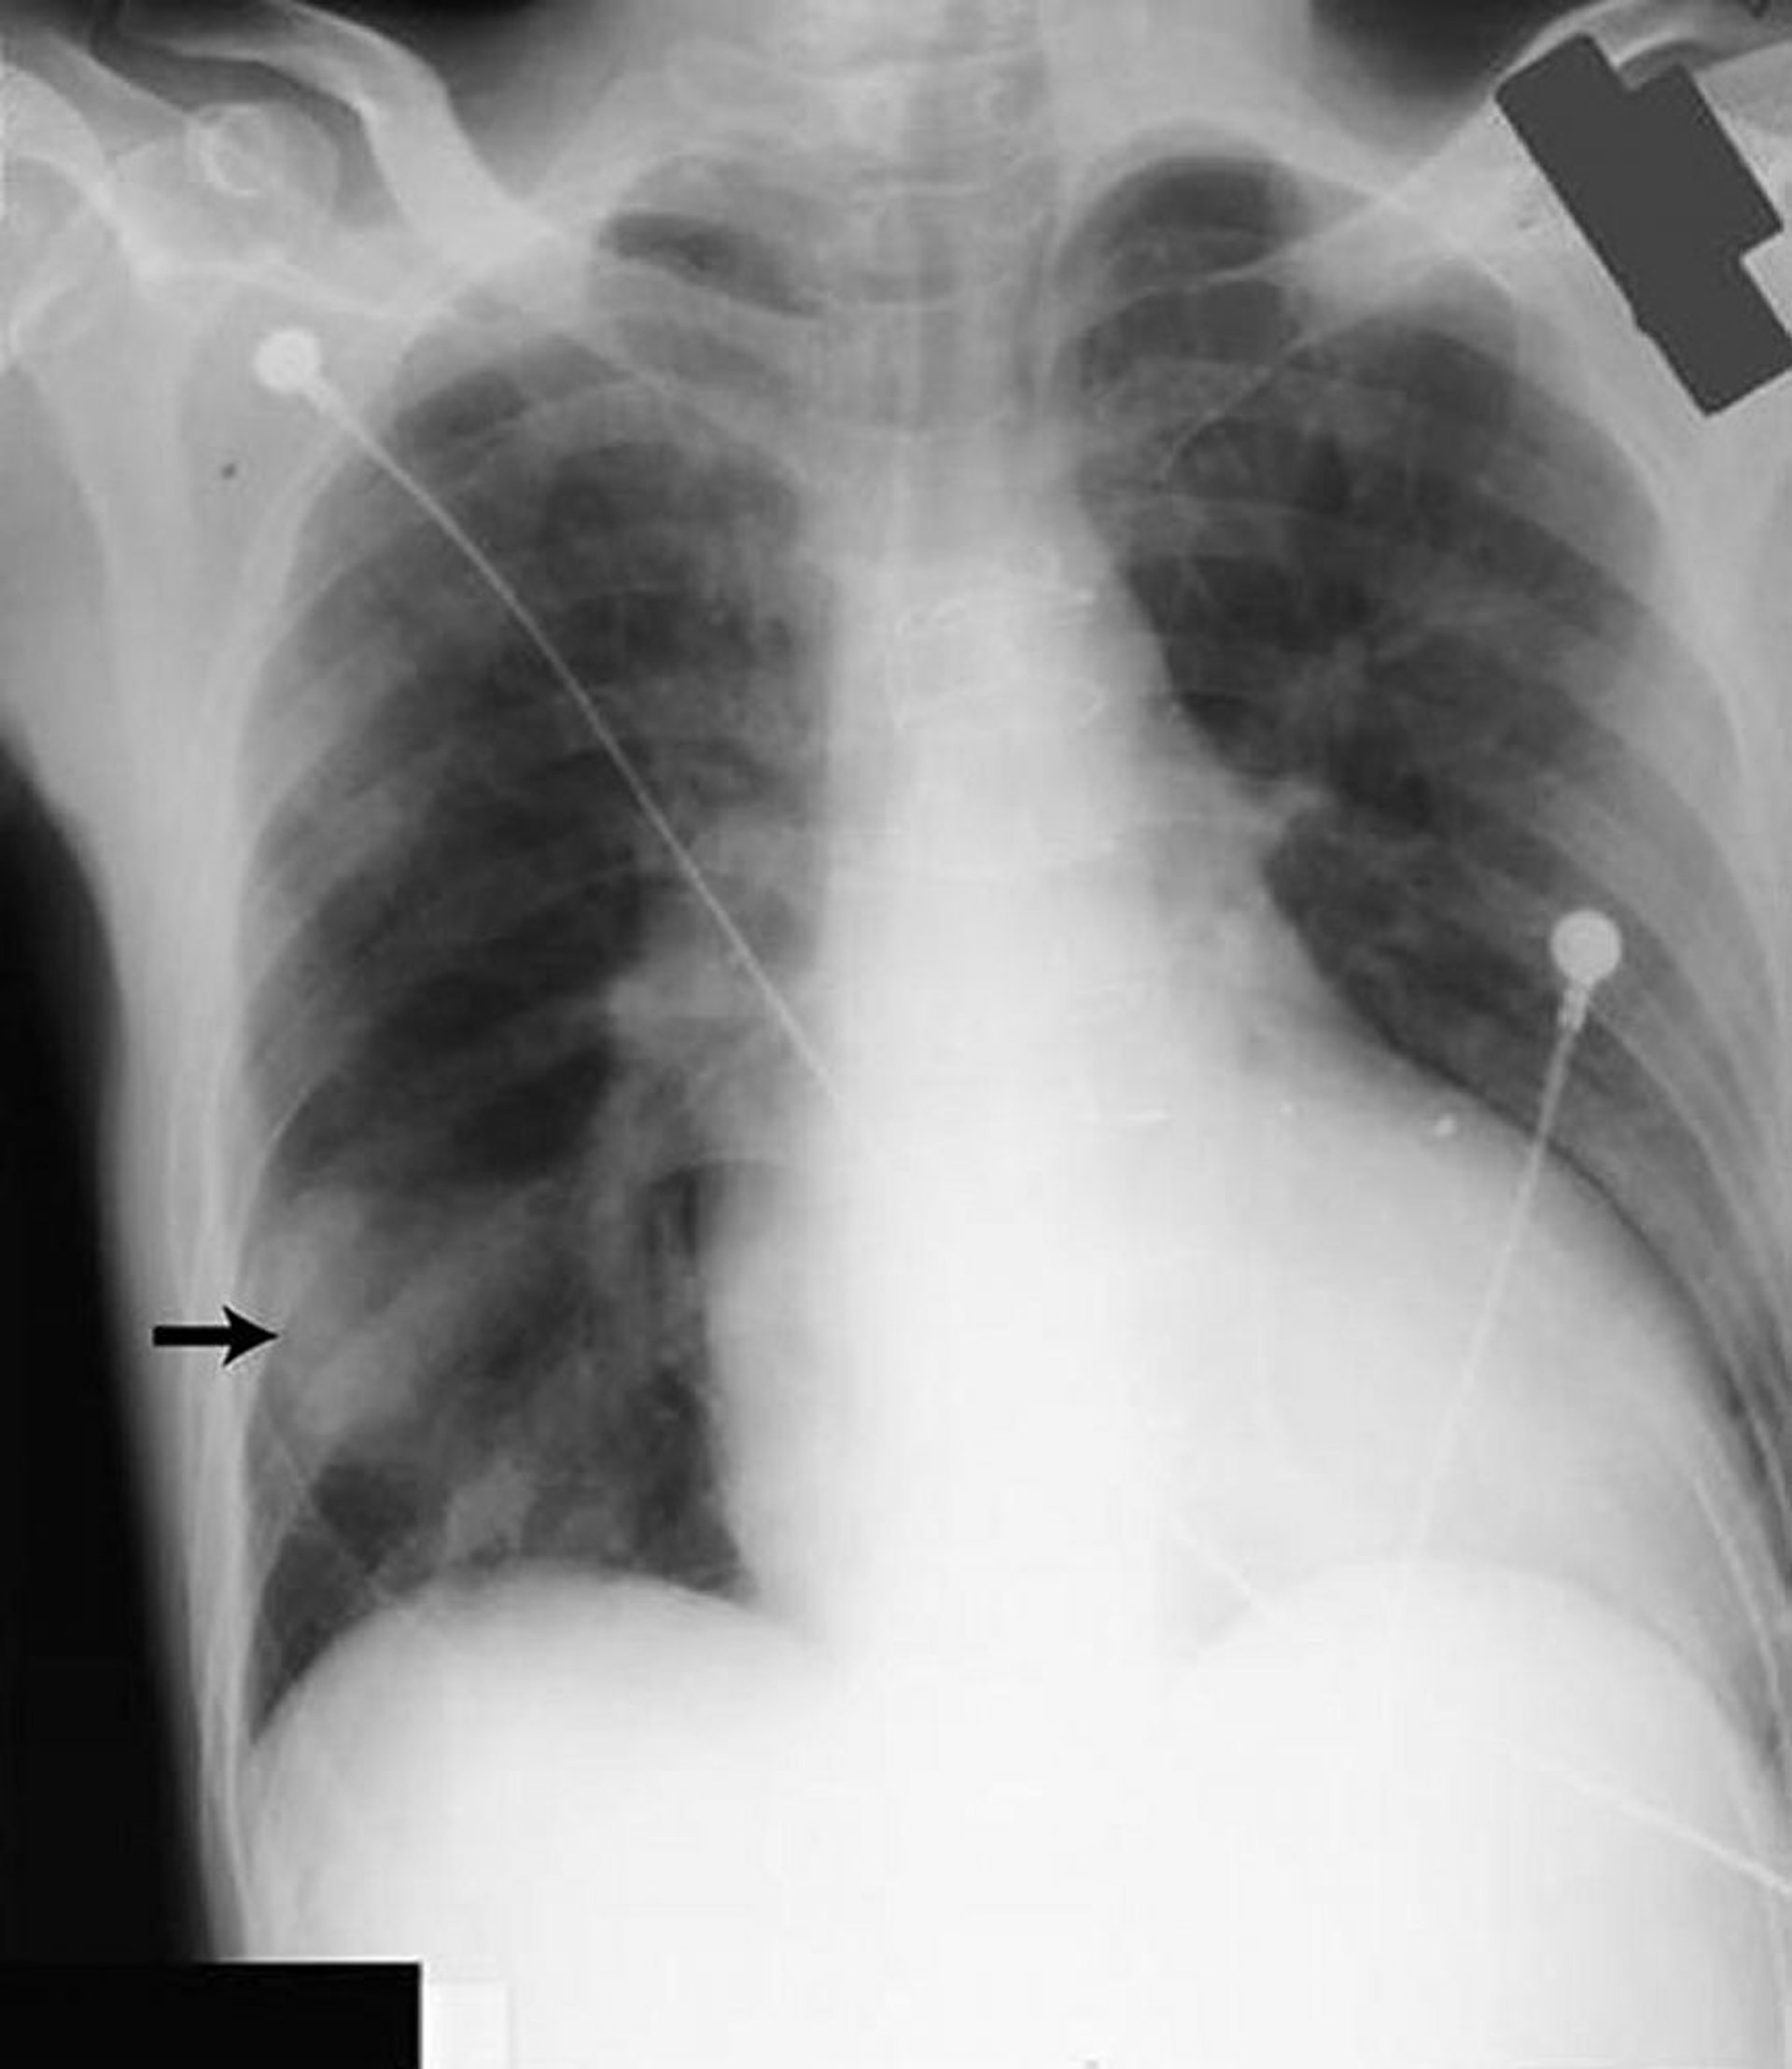

Seudotumor pulmonar

La opacidad en el campo pulmonar inferior derecho (flecha) parece un tumor sólido, pero estaba causada por la presencia de líquido en la cisura mayor en un paciente con insuficiencia cardíaca.